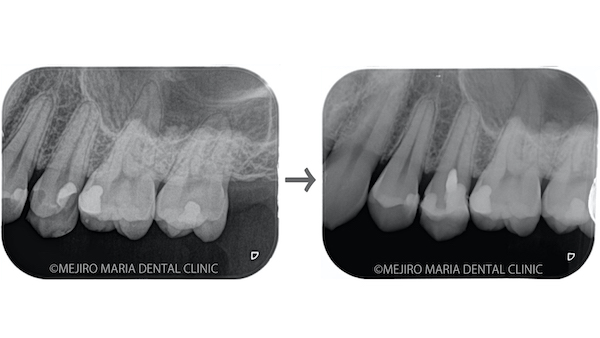

従来法

根管の先(根尖)を切り取った後に、そのままアマルガムという歯科治療用の金属を充填していました。しかし、アマルガムは歯(歯質)とくっつかない性質で封鎖性が悪い材料でした。

また、肉眼で根尖の切断を行っていたため、根尖を斜めに切断することから、骨の削除量や感染部の取り残しが多く、従来法での治療の成功率は20~60%とされています。

現在の方法

根管の先(根尖)を切り取った後に根尖を超音波で洗浄できるようになりました。超音波の洗浄機械の形が進化し、歯肉を切開して露出した根管にアクセスできるようになったためです。また充填剤にはMTAセメントというセメントを使用します。MTAセメントは固まる際に膨張するため、封鎖性が非常に高いのが特徴です。生体親和性が高いので、より緊密な封鎖が可能になりました。

左が従来法、右が現在の方法の歯根端切除術です。 根尖切断の際に角度をつけると、余分な骨を削り生体への侵襲は大きくなります。

また、従来法では根尖側からのアクセス(逆根管形成)もバー(Bur)を使用しており、根管内の細菌の除去が不十分だったことと、封鎖するための材料に厚みがとれなかったことから、失敗につながっていたと考えられます。